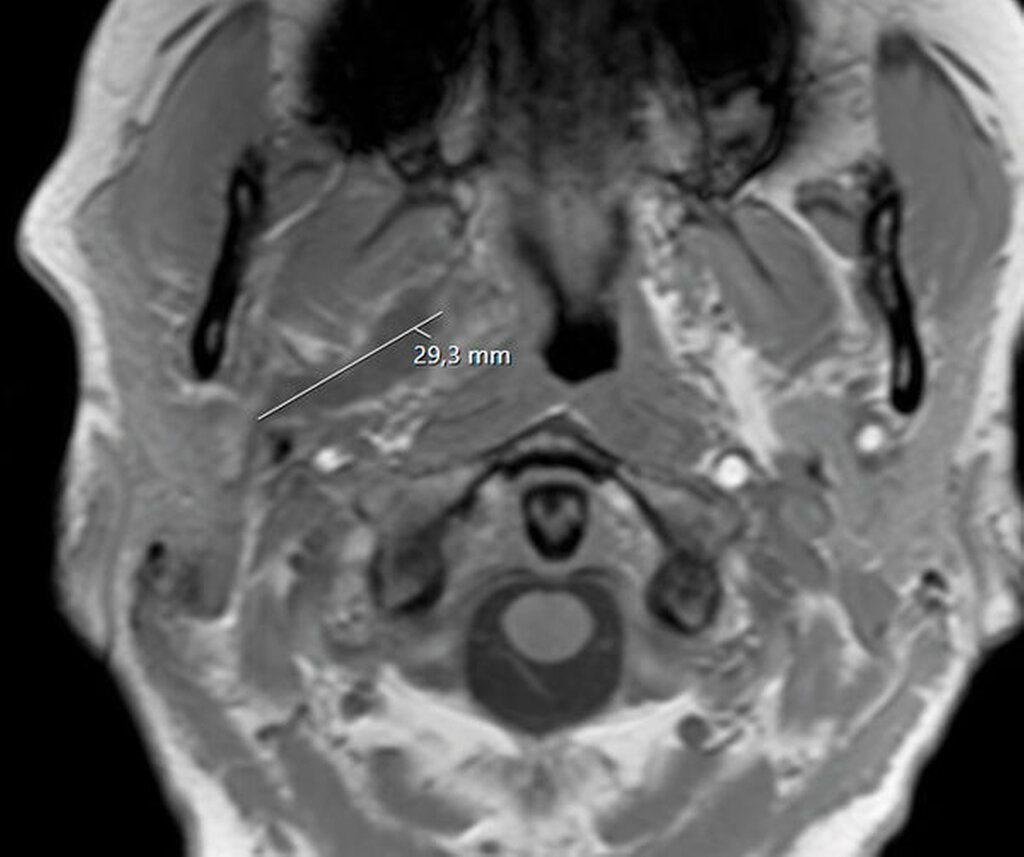

Sonografisch ließ sich weder von submandibulär noch von temporal eine klar abgrenzbare Abszessformation darstellen. Ein initial angefertigtes Labor zeigte stark erhöhte Entzündungsparameter mit einem C-reaktiven Protein von 261 mg/l (Normwert < 5 mg/l) sowie einer Leukozytose von 18/nl (Normwert 3,5–10/nl). Zur weiteren Diagnostik erfolgte die Anfertigung einer Computertomografie des Schädels mit Kontrastmittel. Hier zeigte sich eine circa 14 mm x 45 mm große, liquide Veränderung rechts im Musculus Pterygoideus mediales bis in die Glandula Parotis rechts reichend (Abbildungen 1 und 2). Aufgrund einer flauen Parenchymkontrastierung ließ sich eine Abszessformation nicht sicher ausschließen, die Befunde sprachen in Zusammenschau mit dem zeitlichen Ablauf und der stattgefundenen zahnärztlichen Behandlung jedoch in erster Linie für ein postinterventionelles Hämatom. Eine antikoagulatorische und/oder thrombozytenaggregatorische Therapie konnte ausgeschlossen werden.

Unmittelbar nach der stationären Aufnahme wurde mit der intravenösen Antibiotikatherapie, Glukokortikoidgabe und antiphlogistischen Maßnahmen begonnen. Daraufhin zeigten sich die klinischen und die laborchemischen Entzündungsparameter rückläufig. Die Mundöffnung der Patientin war bereits am Folgetag mit einer Schneidekantendistanz von 40 mm deutlich verbessert. Zur Verlaufskontrolle und Beurteilbarkeit des Weichgewebes im Bereich der Mastikatorloge wurde am zweiten Tag nach stationärer Aufnahme eine Magnetresonanztomografie des Kopfes durchgeführt. Im Vergleich zur initialen Computertomografie der Halsweichteile zeigte sich eine zunehmende Resorption der liquiden ovalären Veränderungen in der rechten Mastikatorloge (Abbildungen 3 und 4). Zum Ausschluss einer otorhinolaryngologischen Pathologie wurde die Patientin konsiliarisch in der Hals-Nasen-Ohrenheilkunde der Universitätsmedizin Mainz vorgestellt. Die Kollegen fanden keine pathologischen Auffälligkeiten, so dass bei radiologisch rückläufigem Befund von einem Hämatom ausgegangen werden konnte. Am vierten Tag nach stationärer Aufnahme konnte die Patientin die Klinik mit nahezu normwertigen Laborparametern verlassen und in die ambulante Nachsorge entlassen werden.